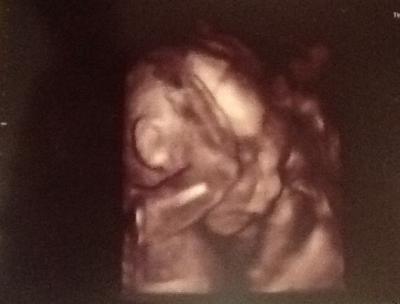

Hey ihr lieben Mamis, FD ist gut verlaufen und die Ärztin war sehr positiv gestimmt da alles an seinem Platz ist und die Plazenta bis jetzt alles gut versorgt!! Sie ist mittlerweile 27cm groß und 470g leicht Wahnsinn wie sehr man jetzt schon an so einem kleinen Wunder hängt... Hab auch ein Bild für euch Schönen Abend für alle!!

Bild zu Heute FD mit positiven Nachrichten... - Forum für März - Mamis

Glückwunsch zum tollen Termin und schön, dass alles gut ist! Das Foto ist ja herzallerliebst

Das freut mich das alles gut ist. Oh ja, das ist echt wahnsinn, hab heute 2. großen US gehabt und verblieb mich jedes Mal aufs Neue. :D Das Bild ist ja total Zucker.

Schön das alles in Ordnung ist und ein tolles Foto habt ihr da